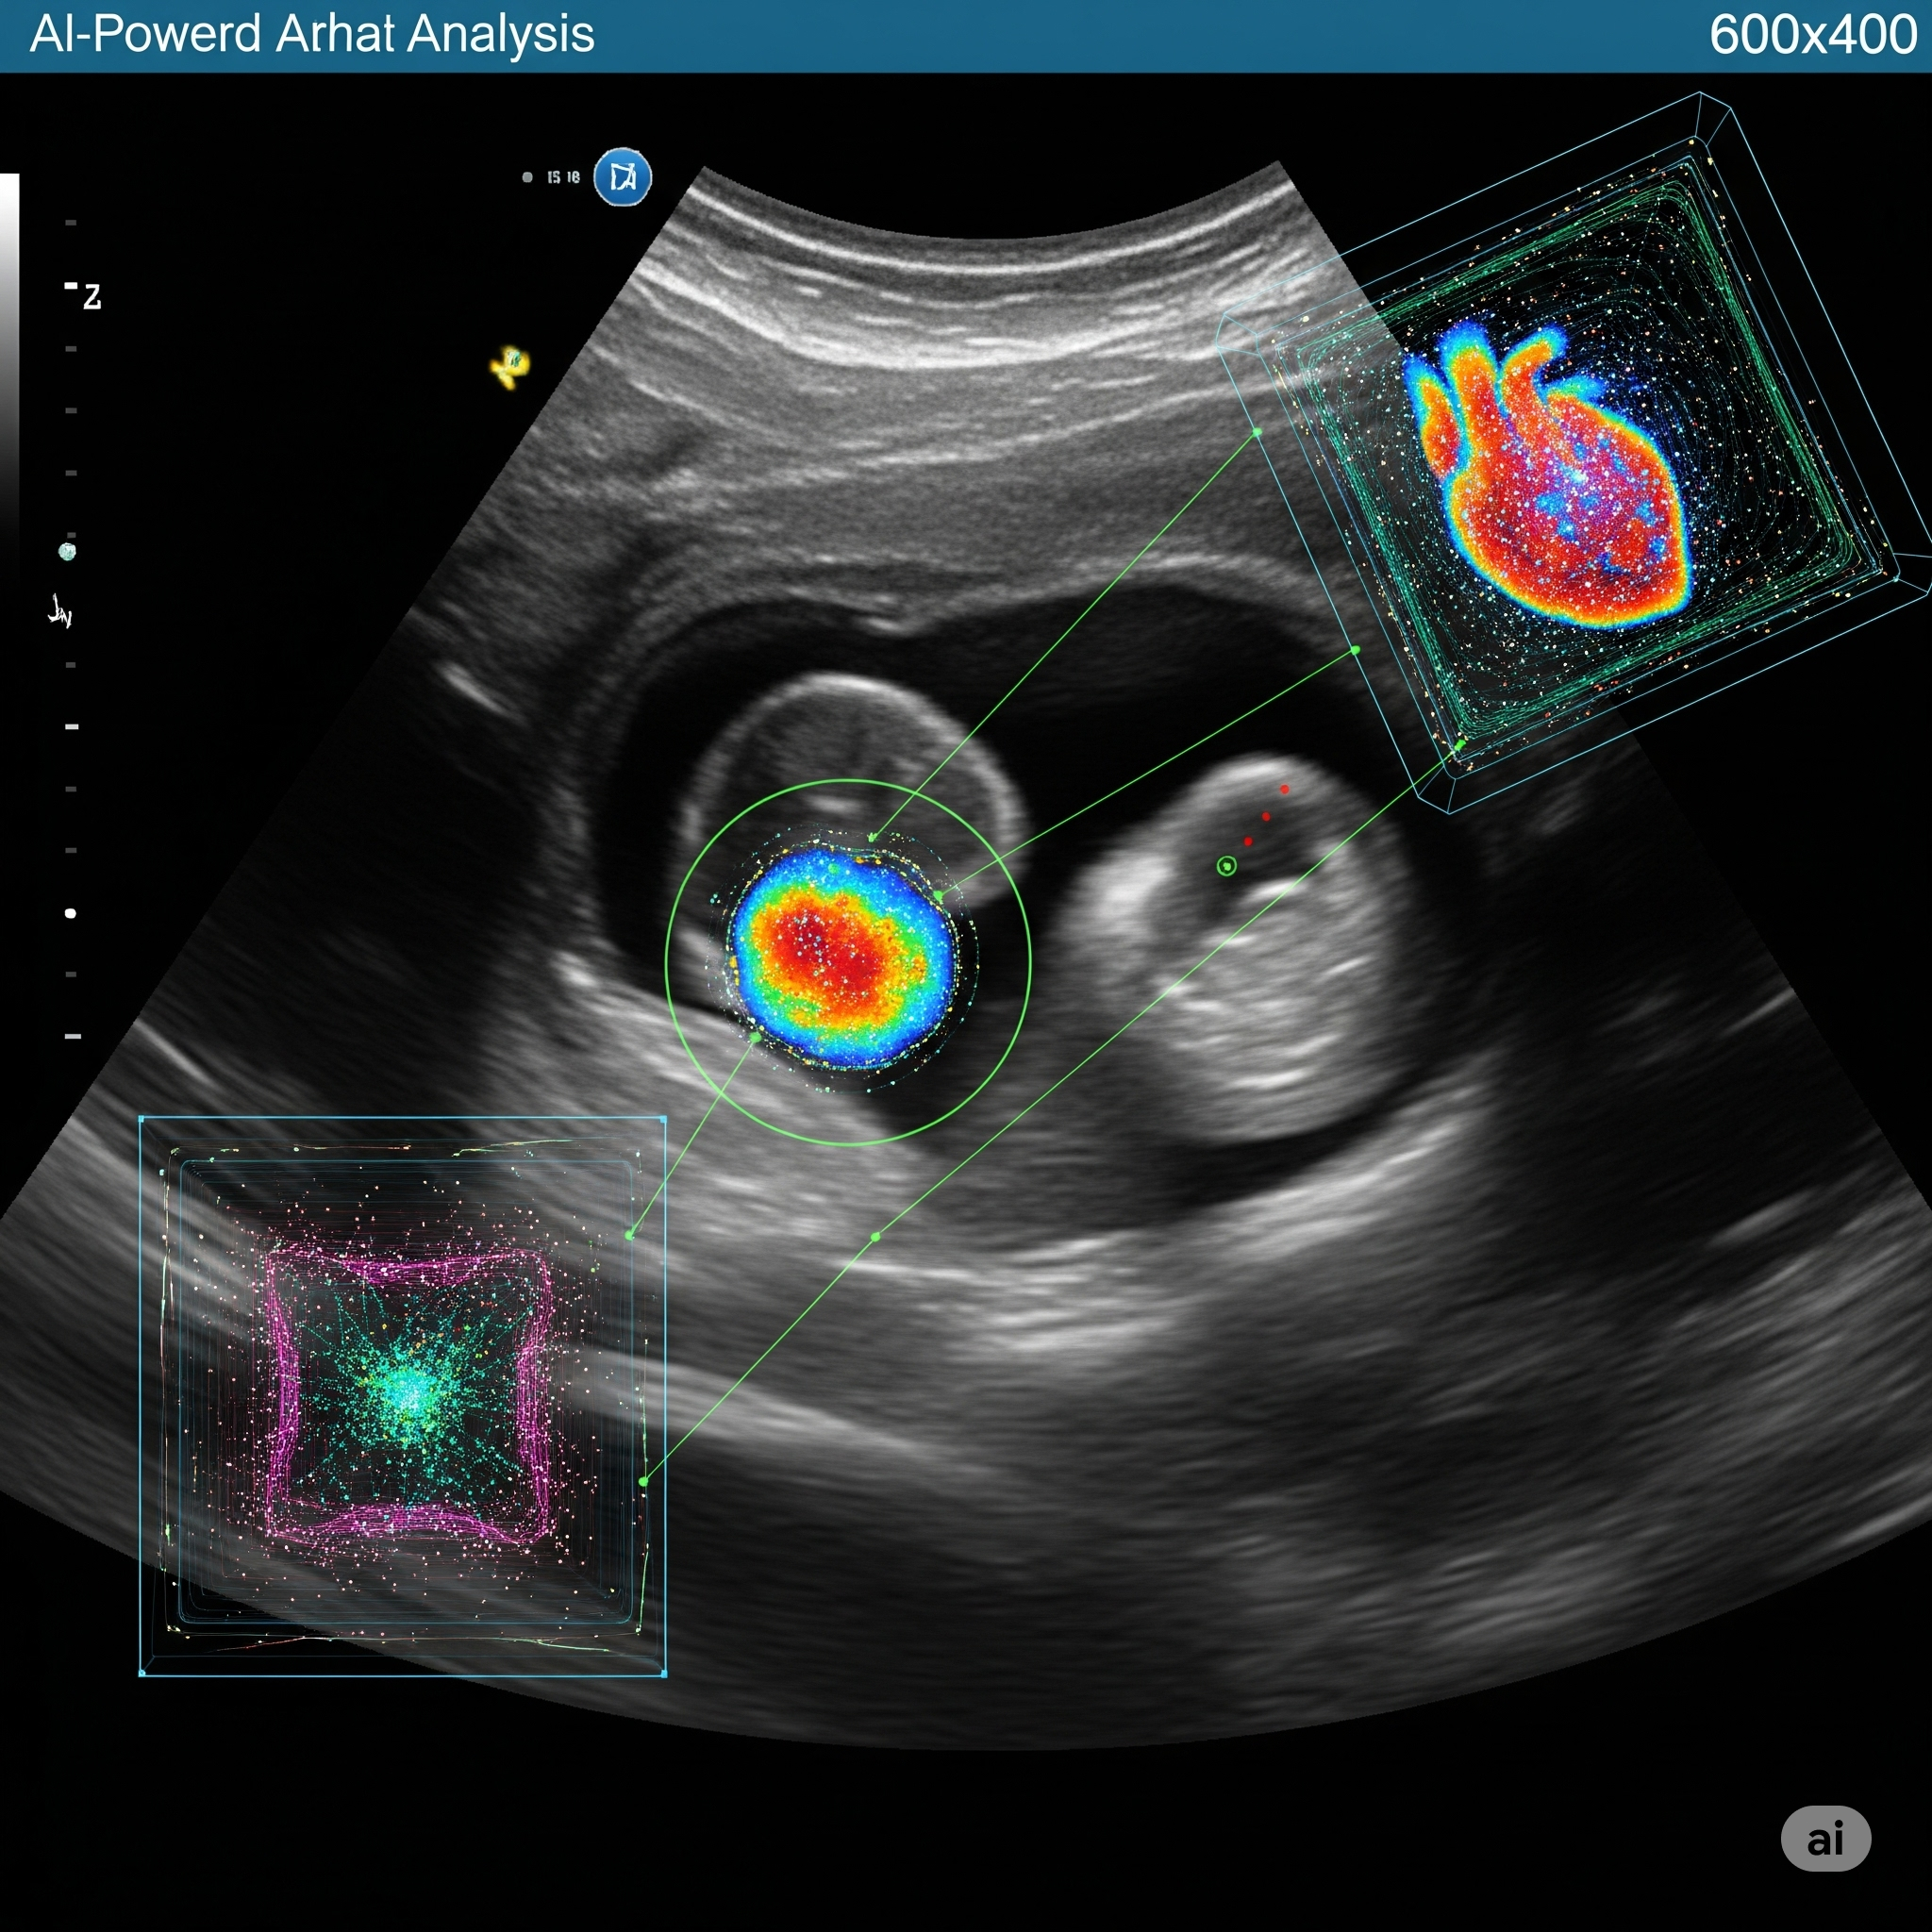

AI Powered Heart Analysis

This vision means AI tools that are not only powerful but also user-friendly, reducing the friction of adoption. By integrating advanced computer vision and machine learning seamlessly into standard prenatal and early childhood screenings, we aim to maximize detection rates and transform the standard of pediatric cardiac care worldwide.